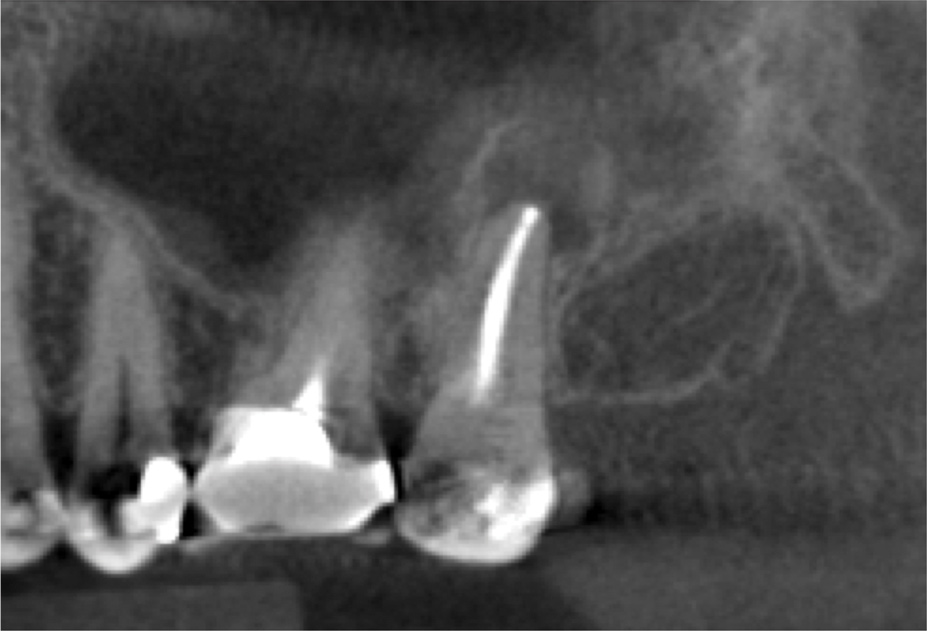

For patients suffering from MSEO, radiographs will reveal a periapical radiolucency with adjacent opacification in the maxillary sinus.12 Additional radiographic findings associated with MSEO include periapical mucositis and periapical osteoperiostitis (PAO). Periapical mucositis refers to mucosal thickening or dome-shaped soft-tissue expansion on the floor of the sinus directly adjacent to the infected root apex.PAO refers to the reactive osteogenesis caused by a local periosteal reaction that expands the sinus periosteum and displaces it upward into the sinus. It appears as a radiopaque "halo" surrounding the root apex (Figure 2 through Figure 4). PAO may be symptomatic and/or accompanied by adjacent mucosal edema and elevated sinus fluid levels.9 If left untreated, PAO can progress and result in a direct communication between the root apex and maxillary sinus.6,13 Unless bilateral odontogenic pathosis is found, the sinus opacifications will usually be unilateral and centered around the odontogenic source. Complete unilateral sinus opacifications may be missed on the CBCT images typically used in endodontics due to their limited or focused field of view (Figure 5). In cases involving complete unilateral sinus opacification, referral to an ENT or oral surgeon is essential to rule out invasive fungal infection or malignancy.2,17,24

(3.) Sagittal slice of CBCT image of the same tooth displaying PAO or “halo lesion” with associated mucositis.

Figure 3